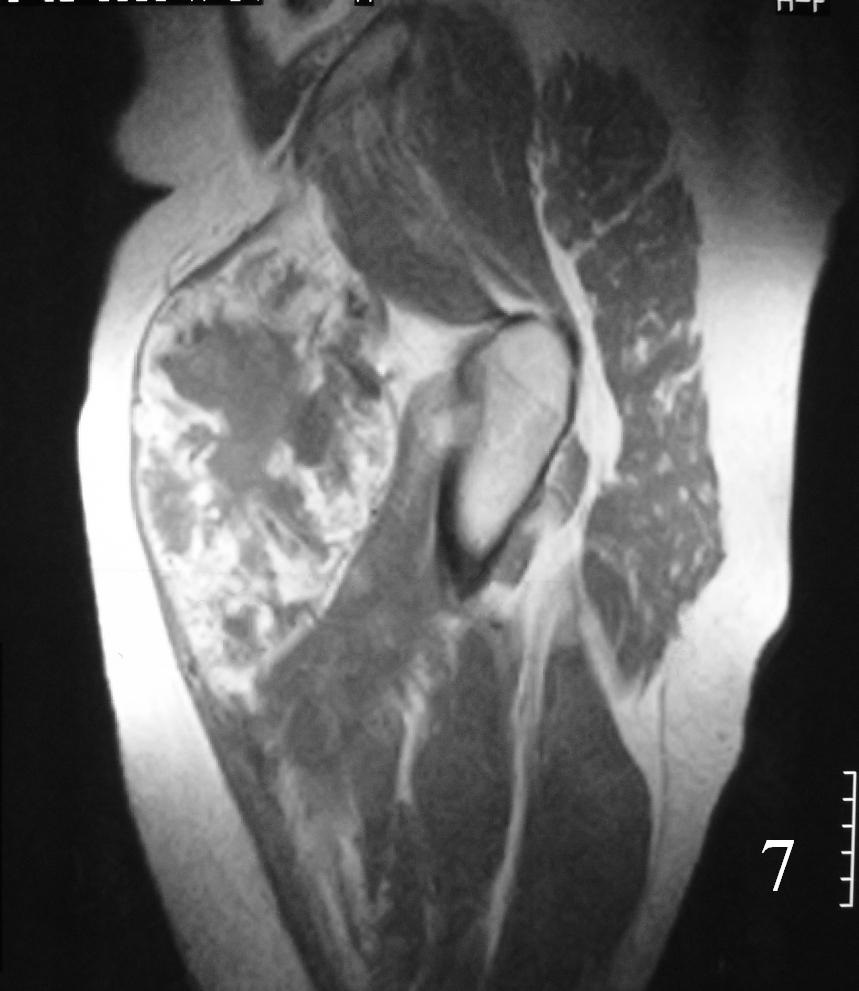

MRI (Fig. 3-7)

Fig. 7

Fig. 3-7 Axial MRI of the lower extremity shows an extraskeletal soft tissue chondrosarcoma in different sequences with and without contrast (Fig. 3, 4, 5). Sagittal MRI (Fig. 6, 7) T1 with-without contrast demonstrates enhancement of the mass